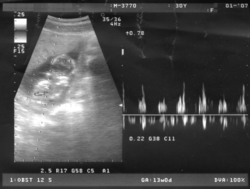

Sigurni znaci trudnoće su postojanje fetusa vidljivog ultrazvučnim nalazom, slušanje srčanih tonova, opipavanje dijelova tijela ploda i prisutnost hormona trudnoće u urinu.

Ljudsko srce počinje kucati u četvrtom tjednu gestacije. Putem ultrazvuka već od šestog tjedna moguće je pratiti srčane tonove fetusa. U petom tjednu dijete ima oko 80 otkucaja u minuti a u devetom tjednu iznosi oko 165 otkucaja. Pokreti disanja opaženi su u desetom tjednu trudnoće. Razvoj pluća kod fetusa započinje u četvrtom tjednu pojavom plućnog pupoljka. Prema većini autora, bubrezi fetusa počinju funkcionirati od trećeg mjeseca gestacije, a do tog zaključka se došlo na osnovi postojanja urina u mokraćnom mjehuru ploda. Do kraja osamnaestog tjedna razvijaju se spolni organi.